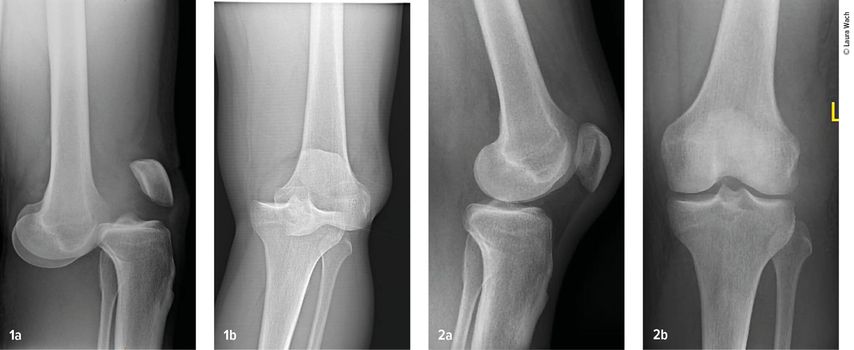

Abb. 1-2: Multiligamentverletzungen am jeweils linken Knie. (1) Klar ersichtlich, (2) leicht zu übersehen

Gefäss- und Nervenverletzungen treten häufig im Zusammenhang mit einer Kniegelenkluxation auf. Henkelmann zitierte einen systematischen Review,3 der 23 Studien mit insgesamt 862 Patienten mit Kniegelenkluxationen umfasst. Bei 171 Patienten (18%) wurden Gefässverletzungen nachgewiesen. Diese kamen bei Patienten mit Schenck-Klassifikation vom Typ IIIL am häufigsten vor. Bei diesem Typ kommt es durch eine posteriore Kniegelenkluxation zur Ruptur beider Kreuzbänder und des lateralen Kollateralbandes (Abb.2 und 3). In 10 der Studien mit insgesamt 272 Patienten wurden auch Nervenverletzungen erfasst. 75 Patienten (25%) waren davon betroffen.